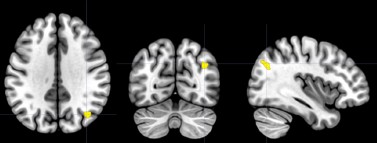

We fully understand that this sample size to reach a medium effect size is seemingly low, and that the18 participants for each group are apparently limited in any case. Upon double-checking these power analyses, we confirmed that this sample size requirement is indeed correct. Please see the G*Power outputs in Author response image 1.

Author response image 1.

Using the GPower software with an estimation of a medium effect size, we determined that a total sample size of N<sub>total</sub> = 34 could reach adequate statistical power. Please see outputs of the GPower in Author response image 1.